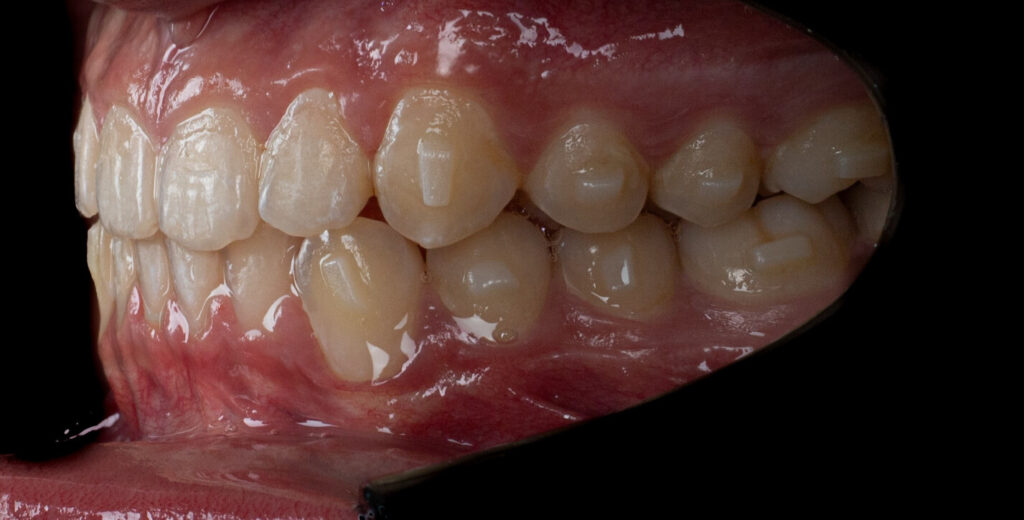

A 13-year-old male patient presented with a deep bite, characterized by near-complete coverage of the mandibular incisors. Clinical evaluation revealed bi-arch crowding, dental rotations, and proclination of the maxillary lateral incisors, contributing to the patient’s esthetic concerns. The facial profile was retrusive, consistent with mandibular retrognathism, and no significant periodontal abnormalities were detected.

The patient presented with a skeletal Class II relationship with bilateral molar and canine Class II and a Class II division 2 dental pattern. The deep bite was associated with anteroinferior crowding and an accentuated Curve of Spee. Facial analysis revealed good symmetry, a slightly increased lower facial third, and a convex profile characterized by mandibular and chin retrusion. Lip competence was mildly reduced, with a decreased nasolabial angle and mentalis hyperactivity, all of which compromised overall facial harmony.